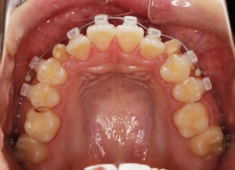

治療開始時

治療中